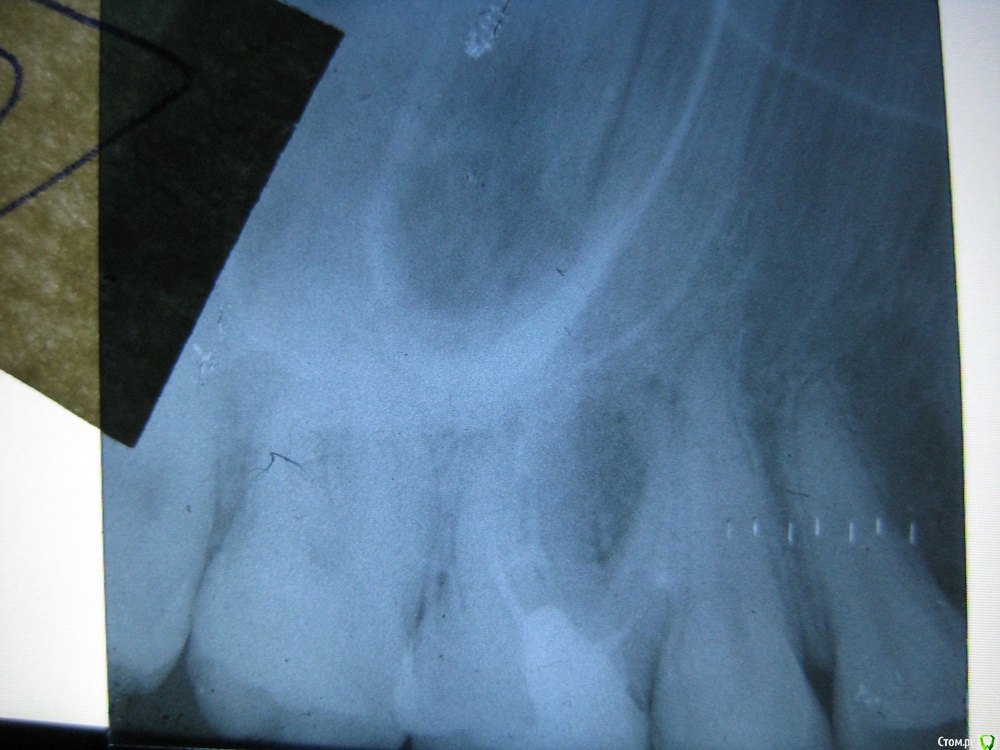

Татьяна1989 Опубликовано 12 февраля, 2018 Поделиться Опубликовано 12 февраля, 2018 (изменено) Здравствуйте!С пятницы почувствовала боль слева в десне ночью,больно было сомкнуть зубы, при надавливании на десну намного повыше зуба очень больно.Утром еще немного больно завтракать, но потом целый день не болело только при пальпации десны выше зуба боль сохраняется.Так и продолжается до сих пор.Сегодня была у врача сделала рентген, сказала гранулема межкорневая и послала к хирург.А он меня к ортодонту (кажется так),ссылаясь на то что доктор оценит можно ли мне сохранить зуб,пролечить с помощью лазера.Так вот доктор посмотрел мой снимок и сказала, что у меня 2 гранулемы, одна сверху а вторая между корней .Сказала пролечить может ту которая между корней, а та которая сверху ее не достать и что я с ней буду жить.Услышав такое я решительно направилась к хирургу удалять зуб.Хирург уже был другой посмотрел мой снимок и начал меня ругать что зачем ты удалять пришла иди лечи его.На снимке он увидел только межкорневую гранулёму, а то что сверху не гранулёма , это по его мнению гайморова пазуха.Фото снимка прилагаю.Вообще что порекомендуете?Спасибо! Изменено 12 февраля, 2018 пользователем Татьяна1989 Ссылка на комментарий

St. Опубликовано 12 февраля, 2018 Поделиться Опубликовано 12 февраля, 2018 Каким образом это возможно? Лазером? И что если перелечить гранулёма рассосется?Вы меня простите за глупые вопросы я простой обыватель.Ничего такого что бы 100% было показанием к удалению я на снимке не вижу. Да, корни частично контактируют с гайморовой пазухой, но это вариант нормального строения. Нет, лазер не нужен)Для того чтобы воспалительный процесс прошел( т.е. рассосалась гранулема) нужно достать старый материал из каналов, их почистить на всю длину, продезенфицировать специальными средствами и запломбировать новым материалом. После этого в примерно 80-85% случаев все проходит. Если лечение не помогло, тогда уже удалять Ссылка на комментарий

Татьяна1989 Опубликовано 12 февраля, 2018 Автор Поделиться Опубликовано 12 февраля, 2018 Ничего такого что бы 100% было показанием к удалению я на снимке не вижу. Да, корни частично контактируют с гайморовой пазухой, но это вариант нормального строения. Нет, лазер не нужен)Для того чтобы воспалительный процесс прошел( т.е. рассосалась гранулема) нужно достать старый материал из каналов, их почистить на всю длину, продезенфицировать специальными средствами и запломбировать новым материалом. После этого в примерно 80-85% случаев все проходит. Если лечение не помогло, тогда уже удалять Мне очень важно скажите у меня все таки одна межкорневая гранулема или еще одна на верхушке корня?Просто мнения докторов разделились. Ссылка на комментарий

DmitrySH Опубликовано 12 февраля, 2018 Поделиться Опубликовано 12 февраля, 2018 Не думаю , но и незнаю насколько он информативен для доктора. Для информативности лучше всего сделать КТ. этот - малоинформативен. Количество гранулем, 1,2,3 - не принципиально для планирования и тактики лечения. В любом случае требуется ревизия всех каналов этого зуба. Ссылка на комментарий